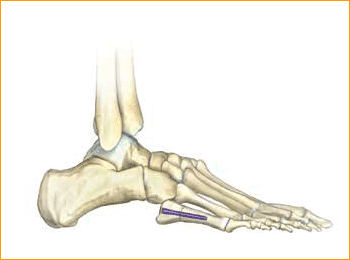

Jones Fracture Technique for 4.5 mm and 5.5 mm Headless Compression screws.

9. SCREW INSERTION

The screw is placed while under fluoroscopic guidance in order to avoid cortical penetration. Postoperative protocol: The patient is placed into a soft dressing, supported by a fiberglass splint. Patients can be made non-weight-bearing for a period of 2–6 weeks postoperatively depending upon Torg type of fracture, bone quality, and underlying morbidities.

Calcaneal Osteotomy Technique for 6.5 mm Headless Compression screws.